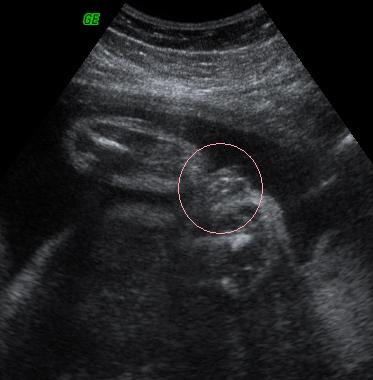

NST: En mar neha most is orulnek, ha minden nap kene mennem. Valahogy olyan megnyugtato hallani a kis szivdobogasat es tudni, hogy minden rendben van vele.